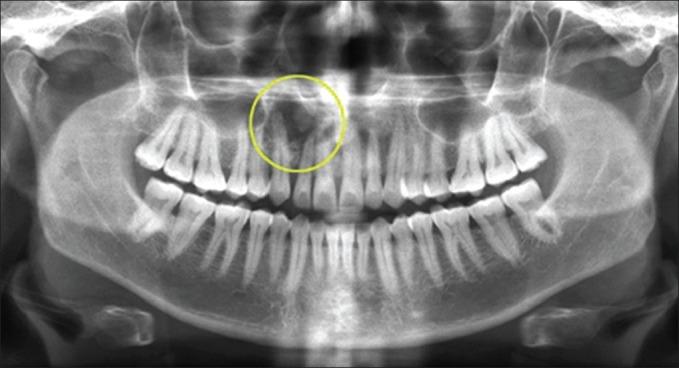

An atypical presentation of Pindborg tumor in anterior maxilla.

Pindborg tumor, the eponymous counterpart of calcifying epithelial odontogenic tumor (CEOT), is a rare benign odontogenic neoplasm that was first described by a Dutch pathologist Jens Jorgen Pindborg in 1955 and accounts for approximately 1% of all odontogenic tumors. Its origin as well as its malignant potential is controversial. This neoplasm is possibly of stratum intermedium origin and occurring predominantly in the mandible of adults. We hereby report a case of Pindborg tumor arising in the premaxilla which is seldom (9 out of 200 cases) documented in the scientific literature.